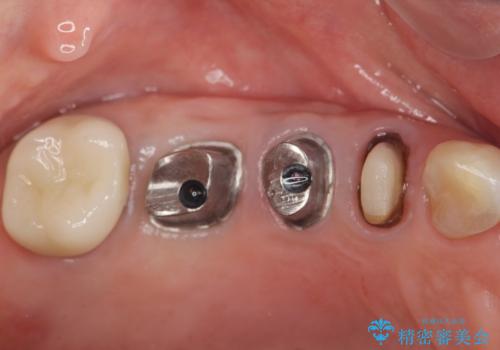

- 費用(概算)

- 125.4万円(インプラント×2・チタンカスタムアバットメント×2・ジルコニアクラウン×4・仮歯×4)費用は治療当時の料金となります